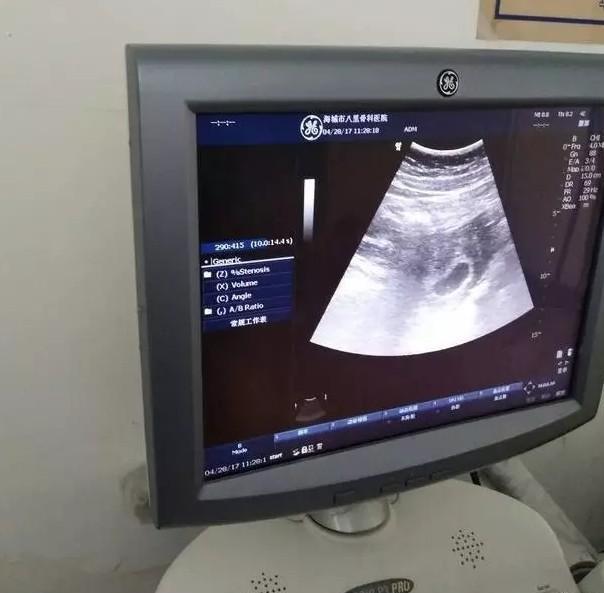

男孩孕囊图50天 男宝,1一3月怀男孩症状

这个胚胎发育的好么,男孩女孩?_停经50天了,大宝儿子

产科老医生教的技巧,从孕囊看男宝女宝,据说非常的准!

50天查的b超孕囊像男孩还是像女孩

孕囊呈现椭圆形为男孩靠谱吗?